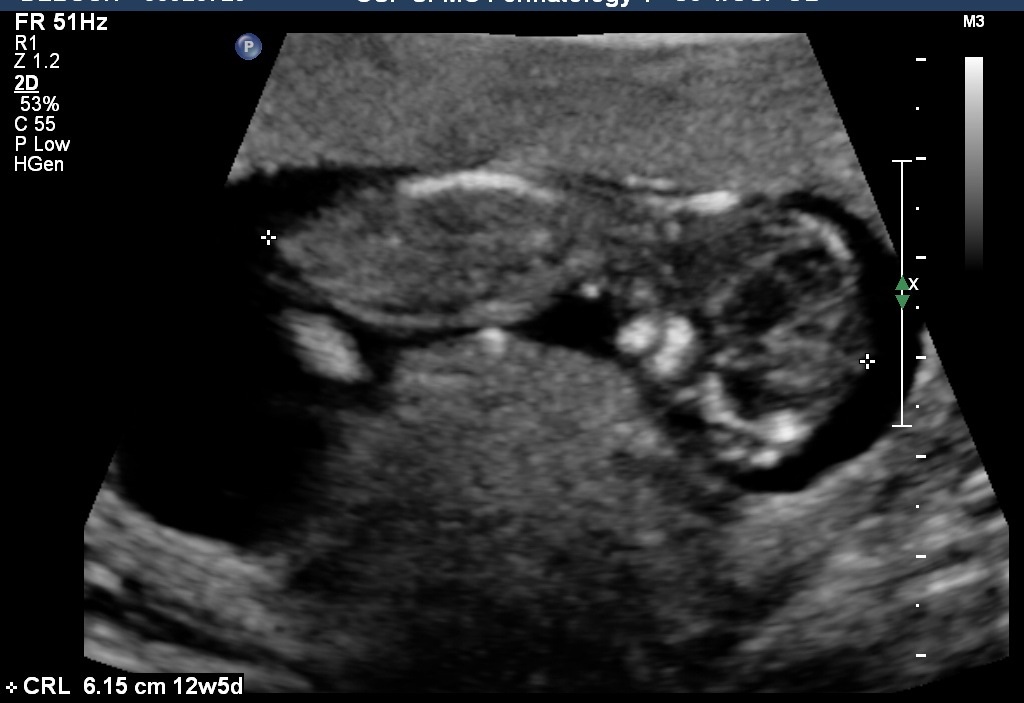

Yeah I wasn't given any good profile shots.:-/ Here's what I have...Attachment 12408Attachment 12409Attachment 12410

Any thoughts? Pretty please?:)

Sure let me try...Attachment 12423Attachment 12424Attachment 12425Attachment 12426